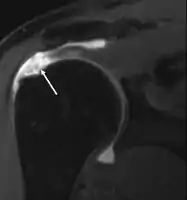

МРТ

Магнитно-резонансная томография (МРТ) и ультразвук[39] сравнимы по эффективности и полезны в диагностике, хотя оба имеют ложноположительный уровень 15–20%.[40] МРТ может надёжно обнаружить большинство разрывов на всю толщину, хотя очень маленькие точечные разрывы можно не заметить. В таких ситуациях МРТ в сочетании с инъекцией контрастного вещества, МР-артрограмма может помочь подтвердить диагноз. Следует понимать, что обычная МРТ не может полностью исключить небольшой разрыв (ложноотрицательный результат), в то время как разрывы частичной толщины не могут быть обнаружены с такой надежностью.[41] Хотя МРТ чувствительна к выявлению дегенерации сухожилия (тендинопатии), она не может надежно отличить дегенеративное сухожилие от частично разорванного сухожилия. Опять же, магнитно-резонансная артрография может улучшить дифференциацию.[41] Её общая чувствительность - 91% (т.е. 9% ложноотрицательных результатов), таким образом магнитно-резонансная артрография является надёжной при обнаружении разрывов частичной толщины вращающей манжеты манжеты.[41] Однако его обычное использование не рекомендуется, поскольку оно связано с введением в сустав иглы с потенциальным риском заражения. Следовательно, тест предназначен для случаев, когда диагноз остается неясным.